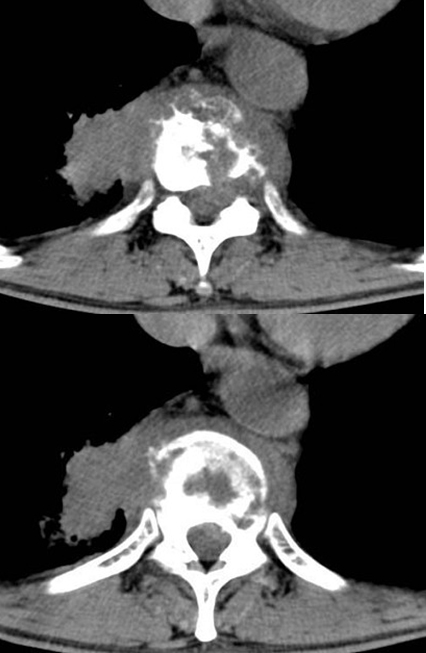

女,34岁,发热,腰部局限性疼痛、活动受限半月余,查体有压痛、叩痛,MRI检查如图,最可能的诊断为()

A.神经纤维瘤

B.脊髓内脓肿

C.神经鞘瘤

D.脊髓空洞

E.蛛网膜囊肿